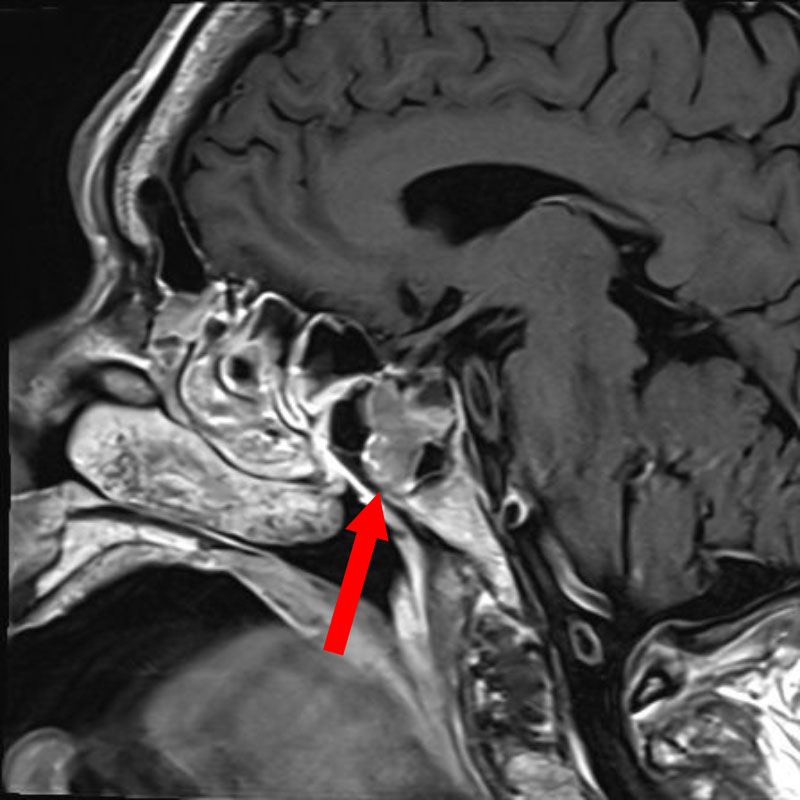

'24年10月

50代

頭蓋咽頭腫

頭蓋内腫瘍摘出術